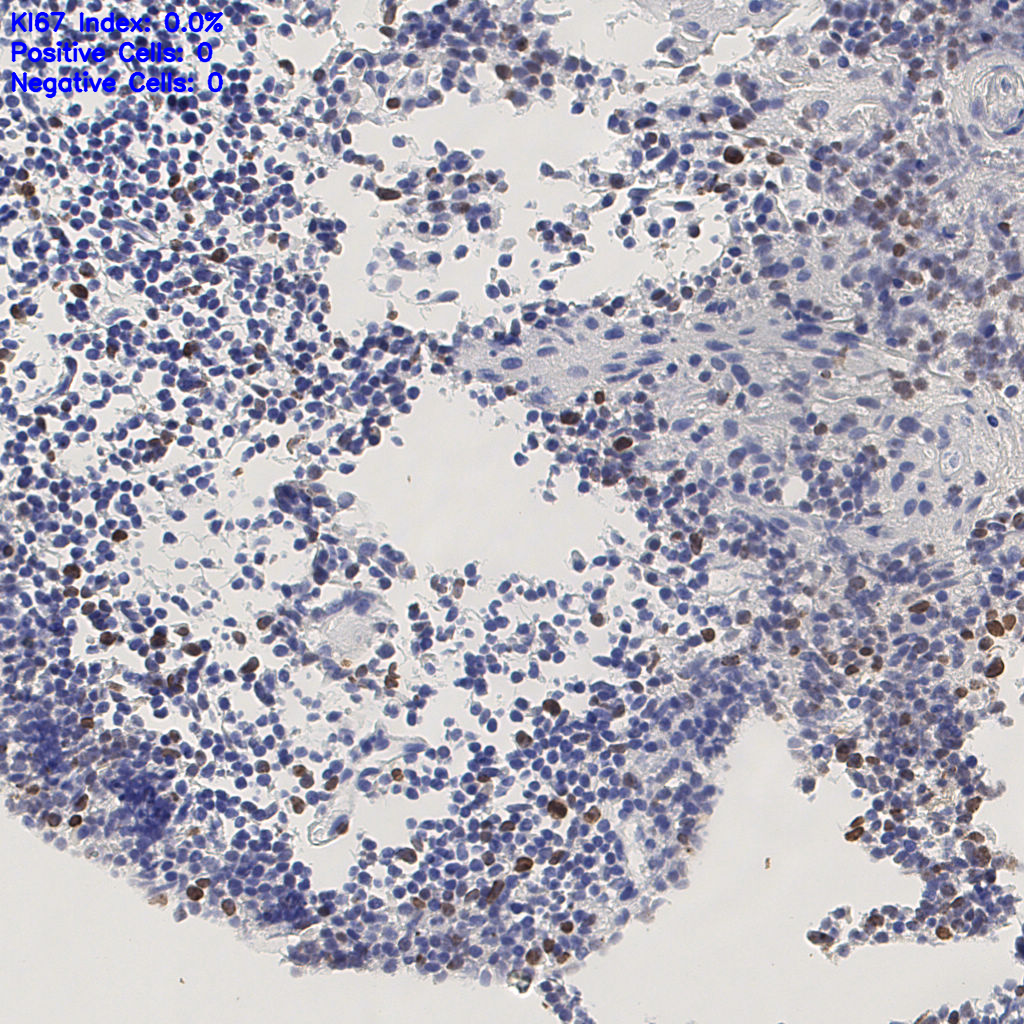

7.85%

Ki67 指数

阴 1104 阳 94

总切片 1953

有效 288

已标记 288

有效率 15%